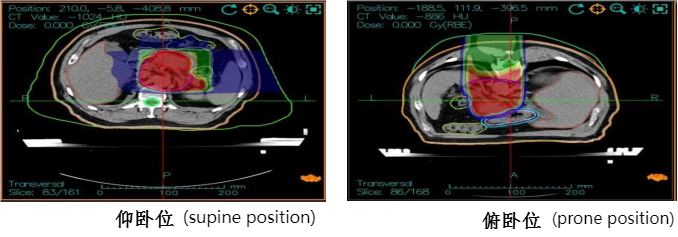

Treatment plan: Carbon ion radiotherapy for pancreatic cancer, supine position with three-field irradiation, total dose: 41.4GyE, 4.6GyE/fraction; prone position PTVboost for local boost dose of 18.4GyE/4 fractions, 4.6GyE/fraction, total prescription dose: PTV 59.8GyE/13 fractions. During treatment, combined with intravenous injection of Nimotuzumab 400mg on day 1 weekly + Gemcitabine 2.0g on days 1 and 8 for chemotherapy. The treatment process proceeded smoothly without significant adverse reactions. Follow-up abdominal MRI after treatment showed a reduction in the pancreatic lesion, with treatment response assessed as partial response (PR).

Carbon ion treatment plan dose distribution map and efficacy evaluation: